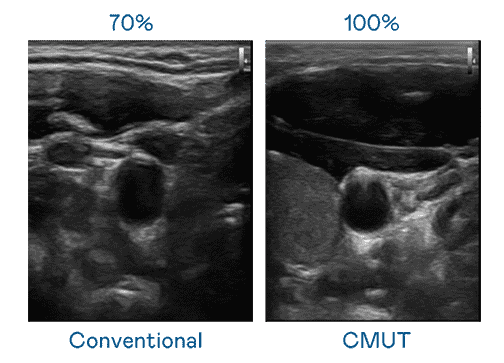

CMUT 技术是一种用电容式微机电元件来产生超音波讯号的技术。。与传统 PZT 压电式技术相比,,CMUT 频宽增加 30%,,,更宽频的超音波讯号让影像解析度大幅提升,,,,是实现高影像品质医疗超音波扫描、、促进精准医疗发展的关键技术。。

大频宽带来超清晰影像

超音波影像的解析度高低,,,首先取决于探头能发出的讯号频宽。。。尊龙集团 CMUT 可提供高清晰的超音波讯号,,,,提供高频宽、、、、高灵敏度、、、影像纹理细节更高的超音波影像,,,协助医护人员缩短影像判读时间及利用精准的医疗影像进行诊断。。